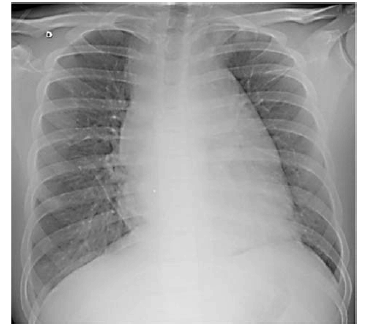

Paciente do sexo masculino, de 16 anos de idade, estudante, compareceu a consulta no posto de saúde, acompanhado da mãe, com queixa de dor no peito. Relatou início dos sintomas após colisão quando jogava futebol. O exame físico foi normal. A imagem a seguir mostra o Raio X do paciente, solicitado por insistência da mãe.

Considerando o caso clínico apresentado, julgue os itens a seguir.